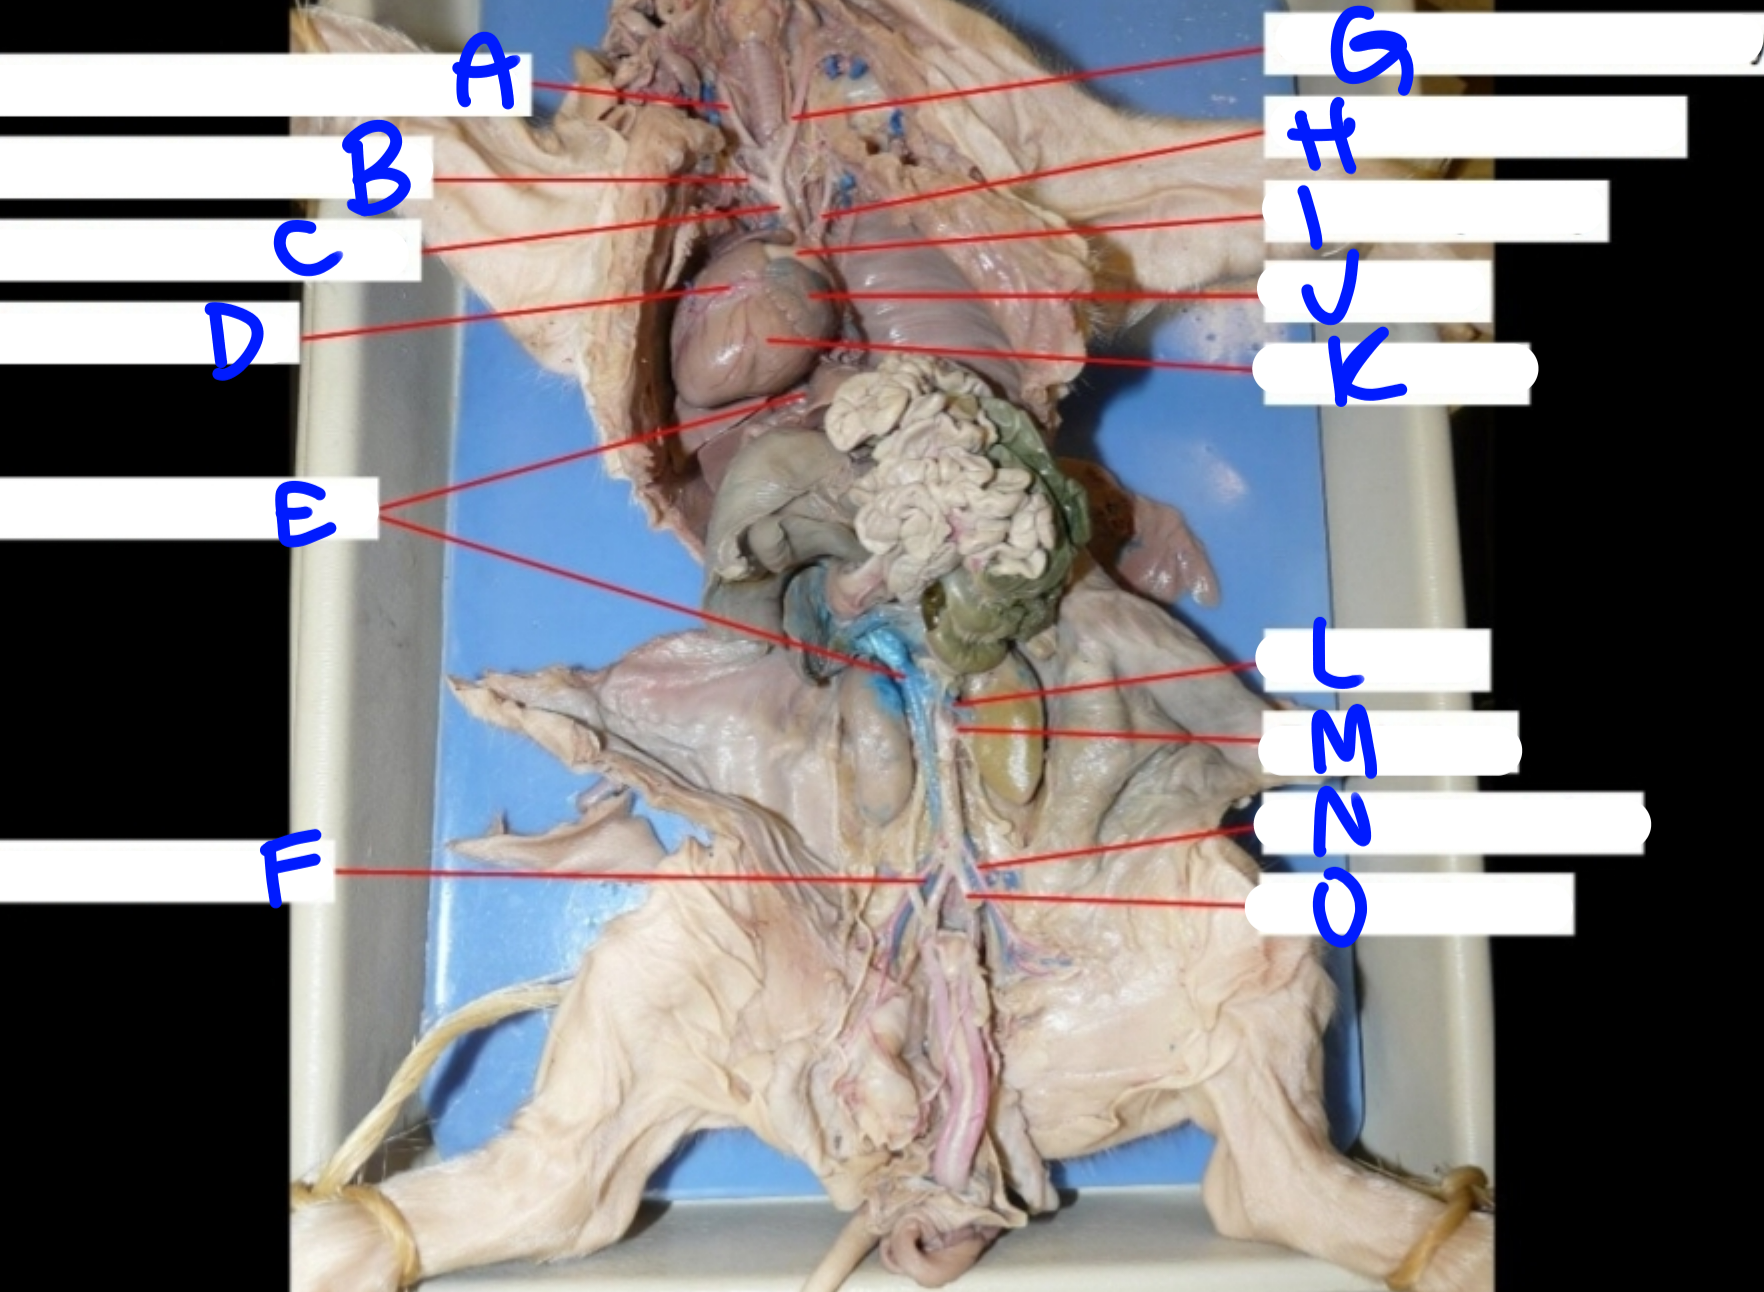

A

Right common carotid artery - delivers oxygenated blood to the head & neck

B

Right subclavian artery - delivers oxygenated blood to the upper body

C

Brachiocephalic artery - delivers oxygenated blood to the upper body

D

Coronary artery - delivers oxygenated blood to the heart

E

Posterior vena cava - carries deoxygenated blood from the lower body to the right side of the heart

G

Left common carotid artery - delivers oxygenated blood to the upper body

H

Left subclavian artery - carries oxygenated blood to the upper body

I

Pulmonary artery - delivers deoxygenated blood from the heart to the lungs

J

Left atrium - delivers oxygenated blood to the left ventricle

K

Left ventricle - delivers oxygenated blood to the systemic circuit

L

Renal vein - delivers blood from the kidney & ureter to the inferior vena cava

M

Renal artery - delivers blood from the kidney & ureter to the inferior vena cava

O

Umbilical artery - carries deoxygenated blood to the placenta